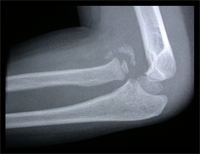

The Monteigga-fracture dislocation is an injury complex where there is fracture of the ulna and dislocation of the radial head. The ulnar fracture may be incomplete or complete and sometimes there is only plastic deformation of the ulna bone. The injury assumes importance due to the frequency with which the radial head dislocation is missed. Acute injuries of the forearm should always be followed by thorough examination of the wrist and elbow.

Biplanar radiographs should include the wrist joint and elbow joint to rule out any joint subluxation or dislocation. Two cases of late presenting Monteigga Fracture — Dislocation. Clinical Features